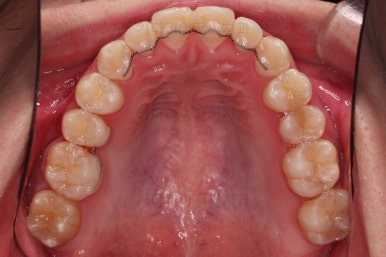

부산교정치과 초진 시 입안의 모습입니다.

앞니가 삐뚤어서 결손치아가 없었더라도 교정치료를 원하셨던 상황이었고요.

오른쪽 어금니 맞물림은 결손치아도 그렇지만 전반적인 앞뒤 차이가 있는 부정교합이 있었어요.